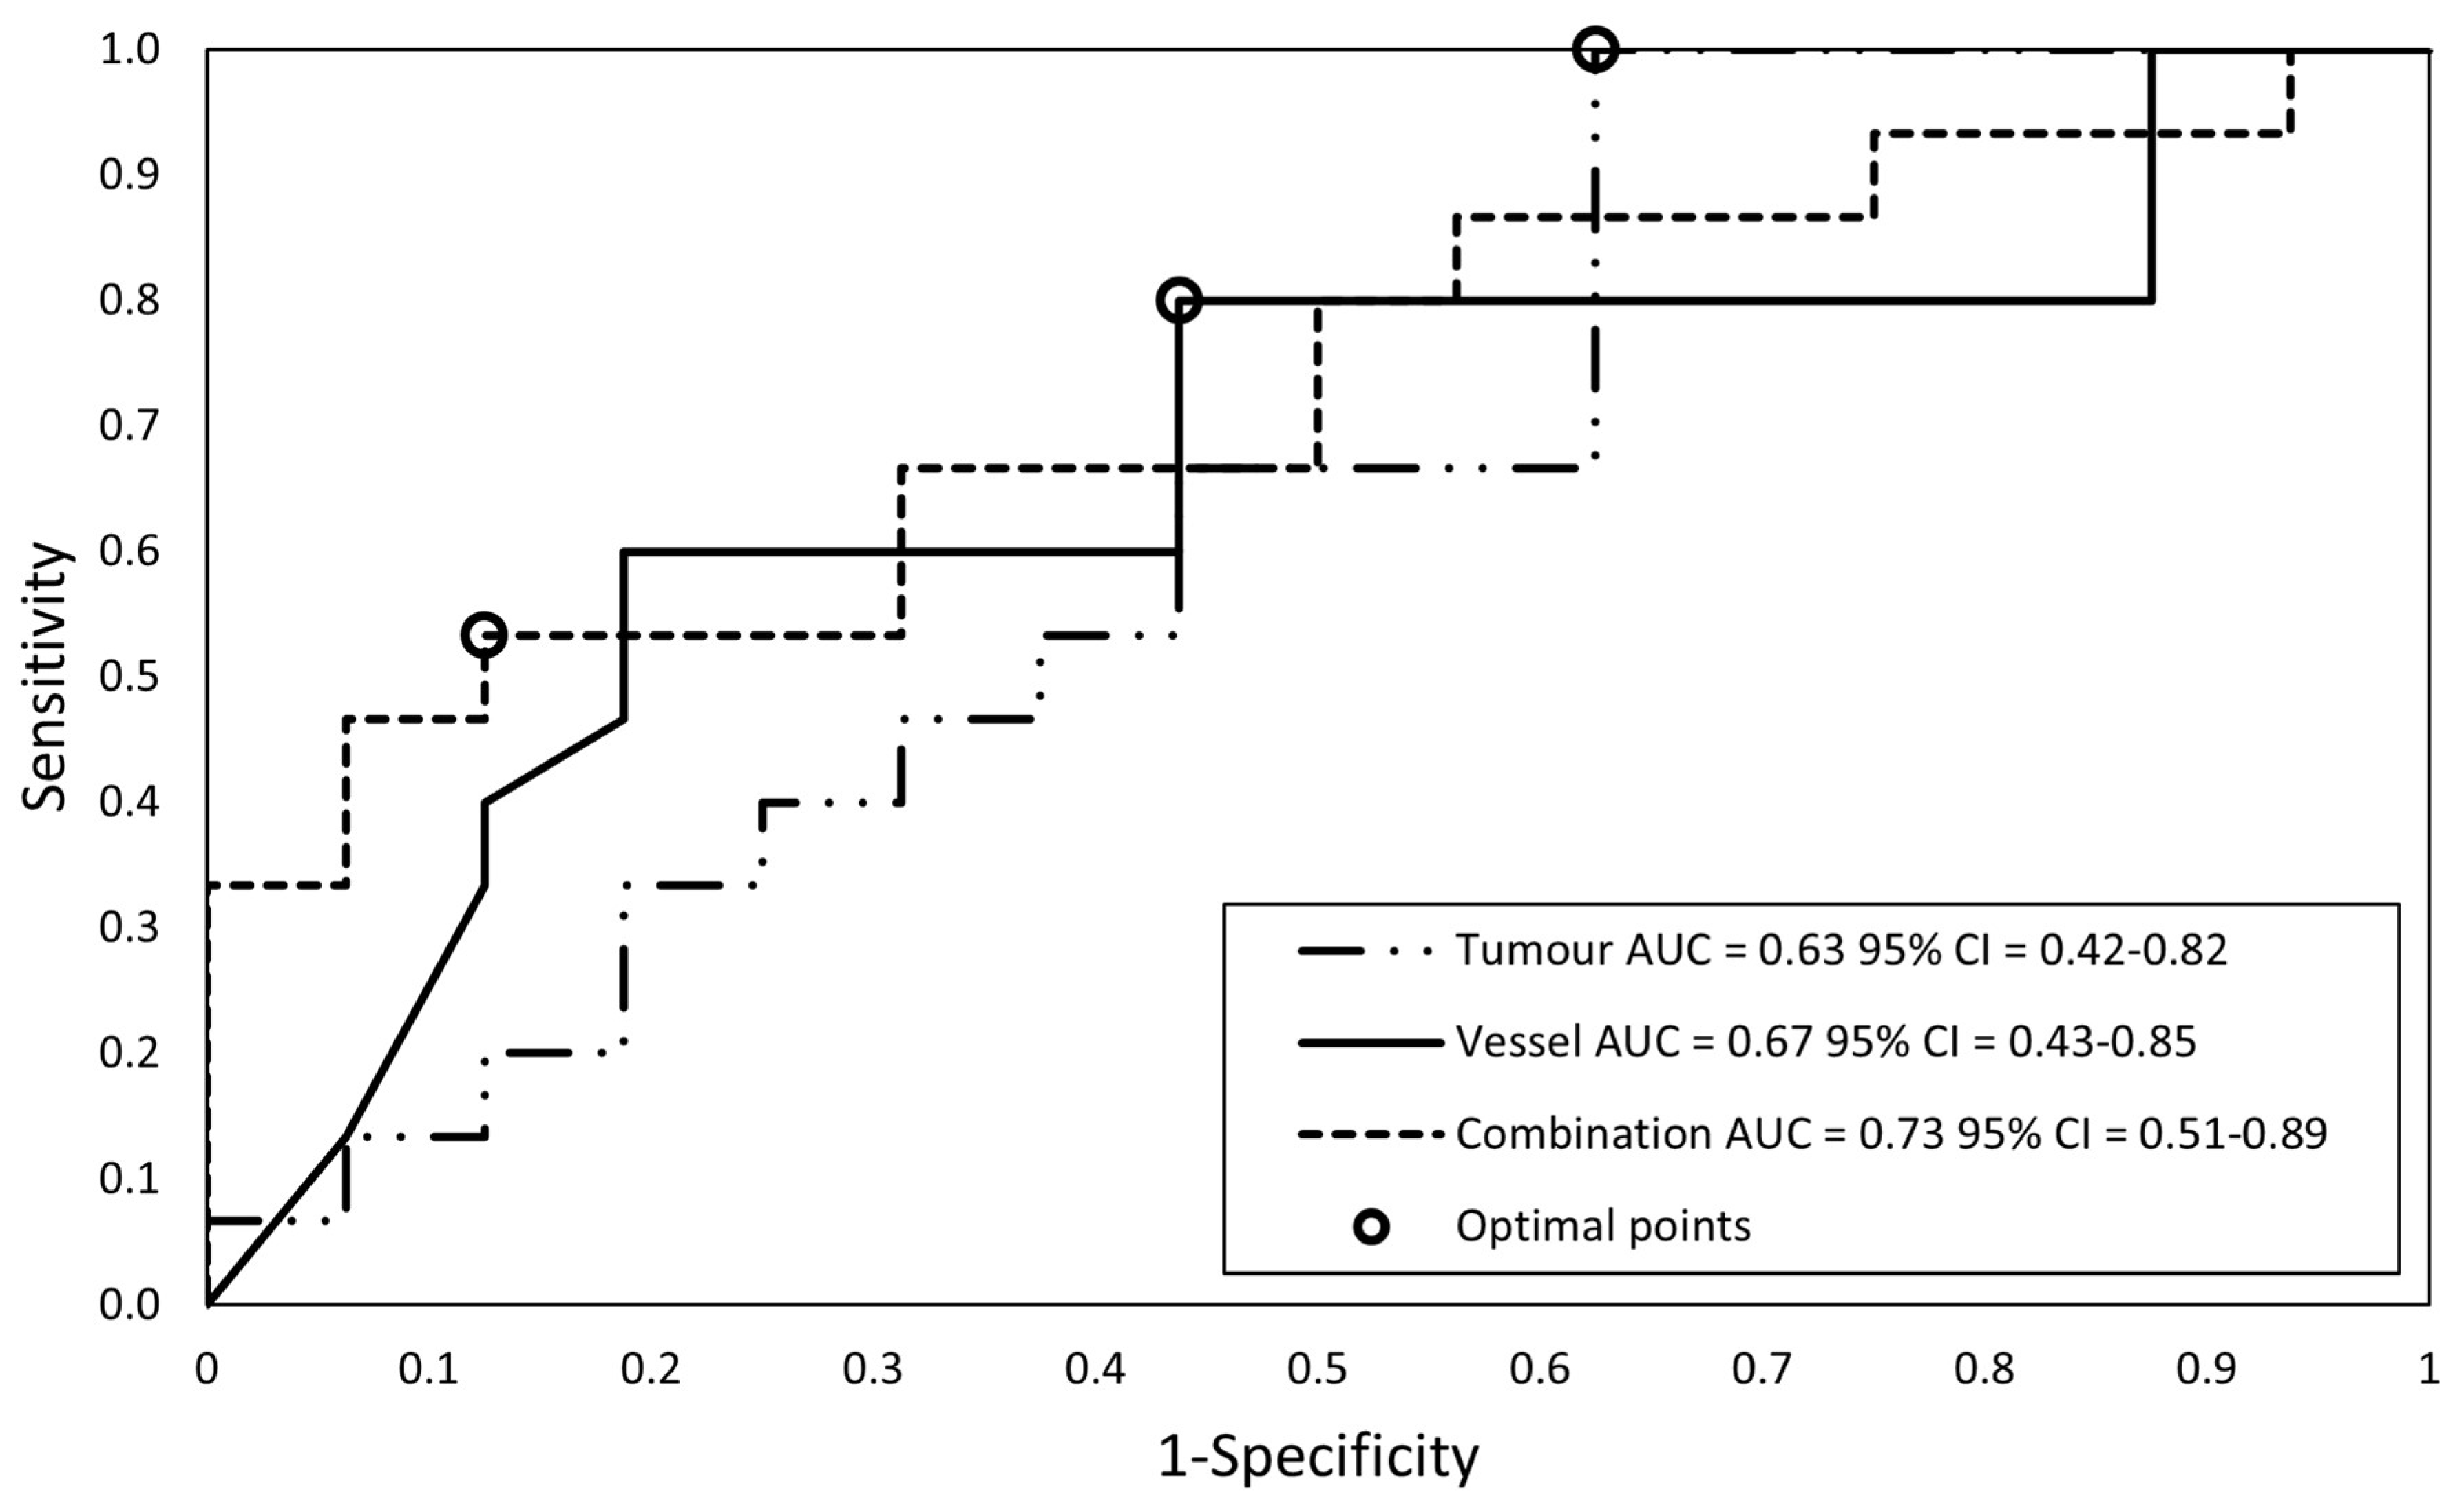

2.7. Subset Analyses: Resection Margin Status

3.3. Subset Analyses: Resection Margin Status

| Model | Sensitivity | Specificity | PPV | NPV | AUC |

| (1) Tumor features | 0.63 (0.42–0.82) | ||||

| Test set, N = 7 | 80% (28–99%) | 0% (0–84%) | 67% (56–76%) | − | |

| (2) Vessel features | 0.67 (0.43–0.85) | ||||

| Test set, N = 7 | 80% (28–99%) | 100% (16–100%) | 100% (−) | 67% (26–92%) | |

| (3) Combined features | 0.73 (0.51–0.89) | ||||

| Training set N = 31 | 53% (27–79%) | 88% (62–98%) | 80% (50–94%) | 67% (53–78%) | |

| Test set, N = 7 | 80% (28–99%) | 50% (1–99%) | 80% (48–94%) | 50% (10–90%) |